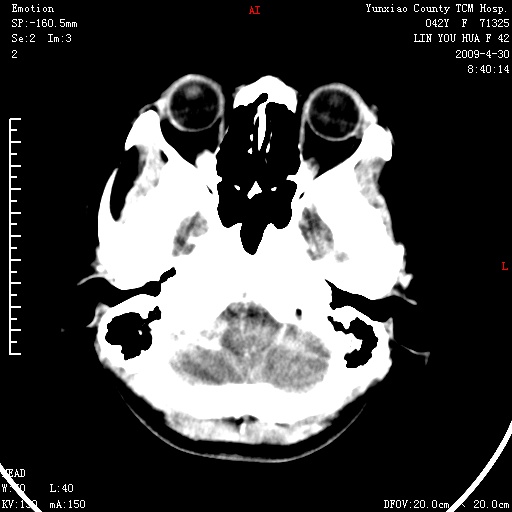

右侧桥小脑角区肿瘤,高密度囊变有显著强化,骨窗见内听道显著扩大,考虑听神经瘤可能性大

1)右侧听神经瘤。2)阻塞性脑积水。

内听道扩大,支持考虑听神经瘤可能性大。